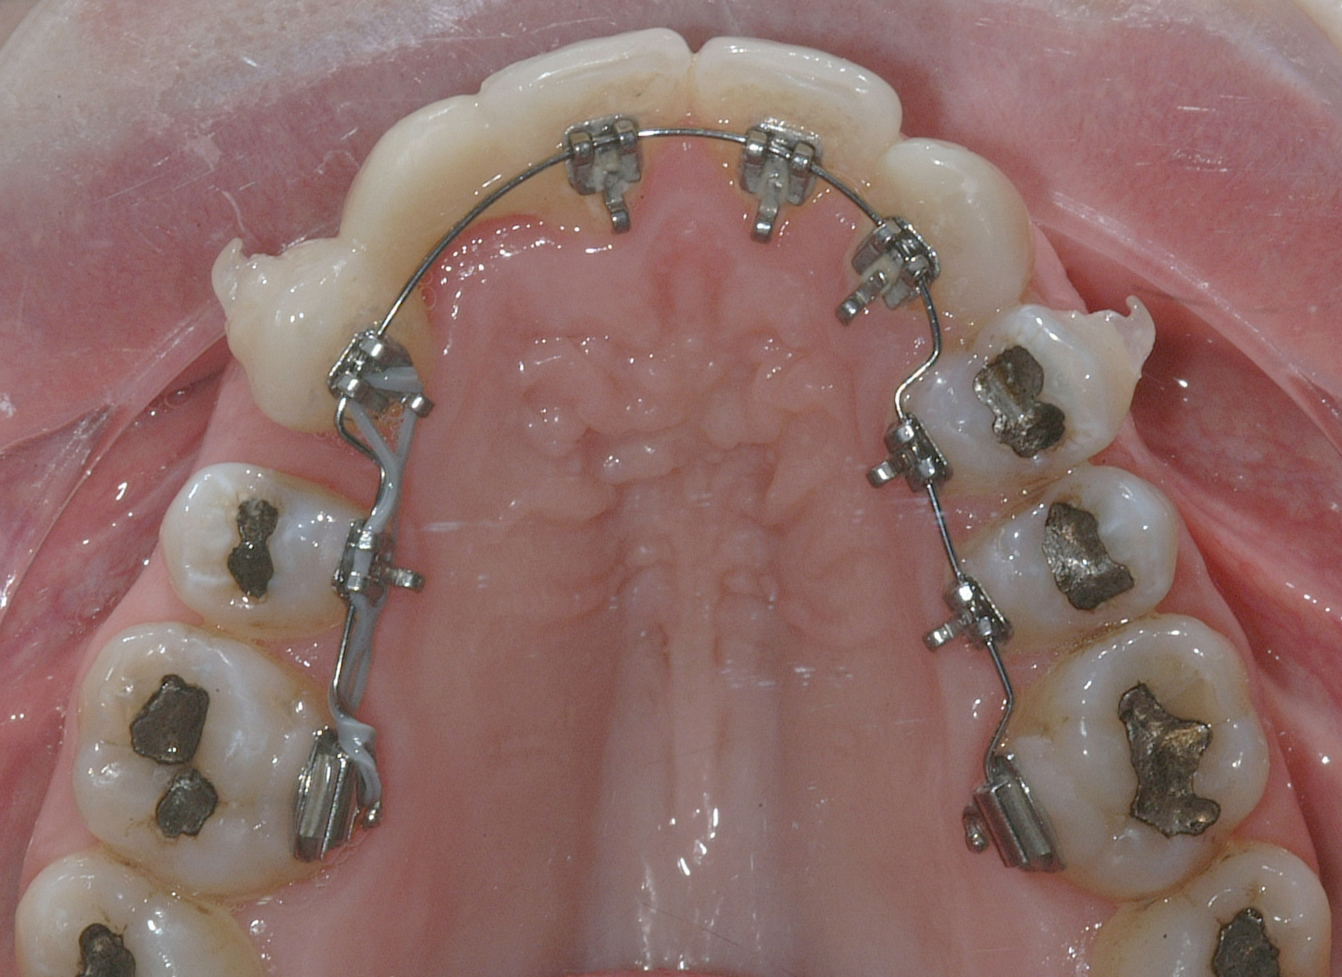

Il protocollo terapeutico ha previsto l’estrazione del primo premolare inferiore sinistro (3.4) e del primo superiore destro (1.4), l’applicazione di una apparecchiatura fissa linguale 2D e di una meccanica asimmetrica di ancoraggio e movimento ortodontico a entrambe le arcate (Figure 3a-b).

Il trattamento è iniziato con l’estrazione dei due premolari in unica seduta in anestesia locale e l’applicazione simultanea, dopo una settimana, della apparecchiatura linguale inferiore e superiore, non essendoci problemi di overbite e potenziali interferenze in occlusione tra l’apparecchiatura superiore e i frontali inferiori. All’arcata superiore è stata effettuata una iniziale chiusura dello spazio estrattivo con forze molto leggere in ancoraggio medio su arco .014” Nichel-Titanio e successivamente .016” Nichel-Titanio, bondato in prima fase per maggior stabilità direttamente sulla superficie mesiale di 2.4.

Nota tecnica: il movimento iniziale di distalizzazione della corona di 1.3 mediante tipping distale (vista la posizione radicolare iniziale) è stato ottenuto con una catenella elastica leggera inserita su 1.6, 1.5 e ancorata su 1.3, abbracciando per maggior controllo l’aletta disto-occlusale e quella gengivale del bracket linguale.